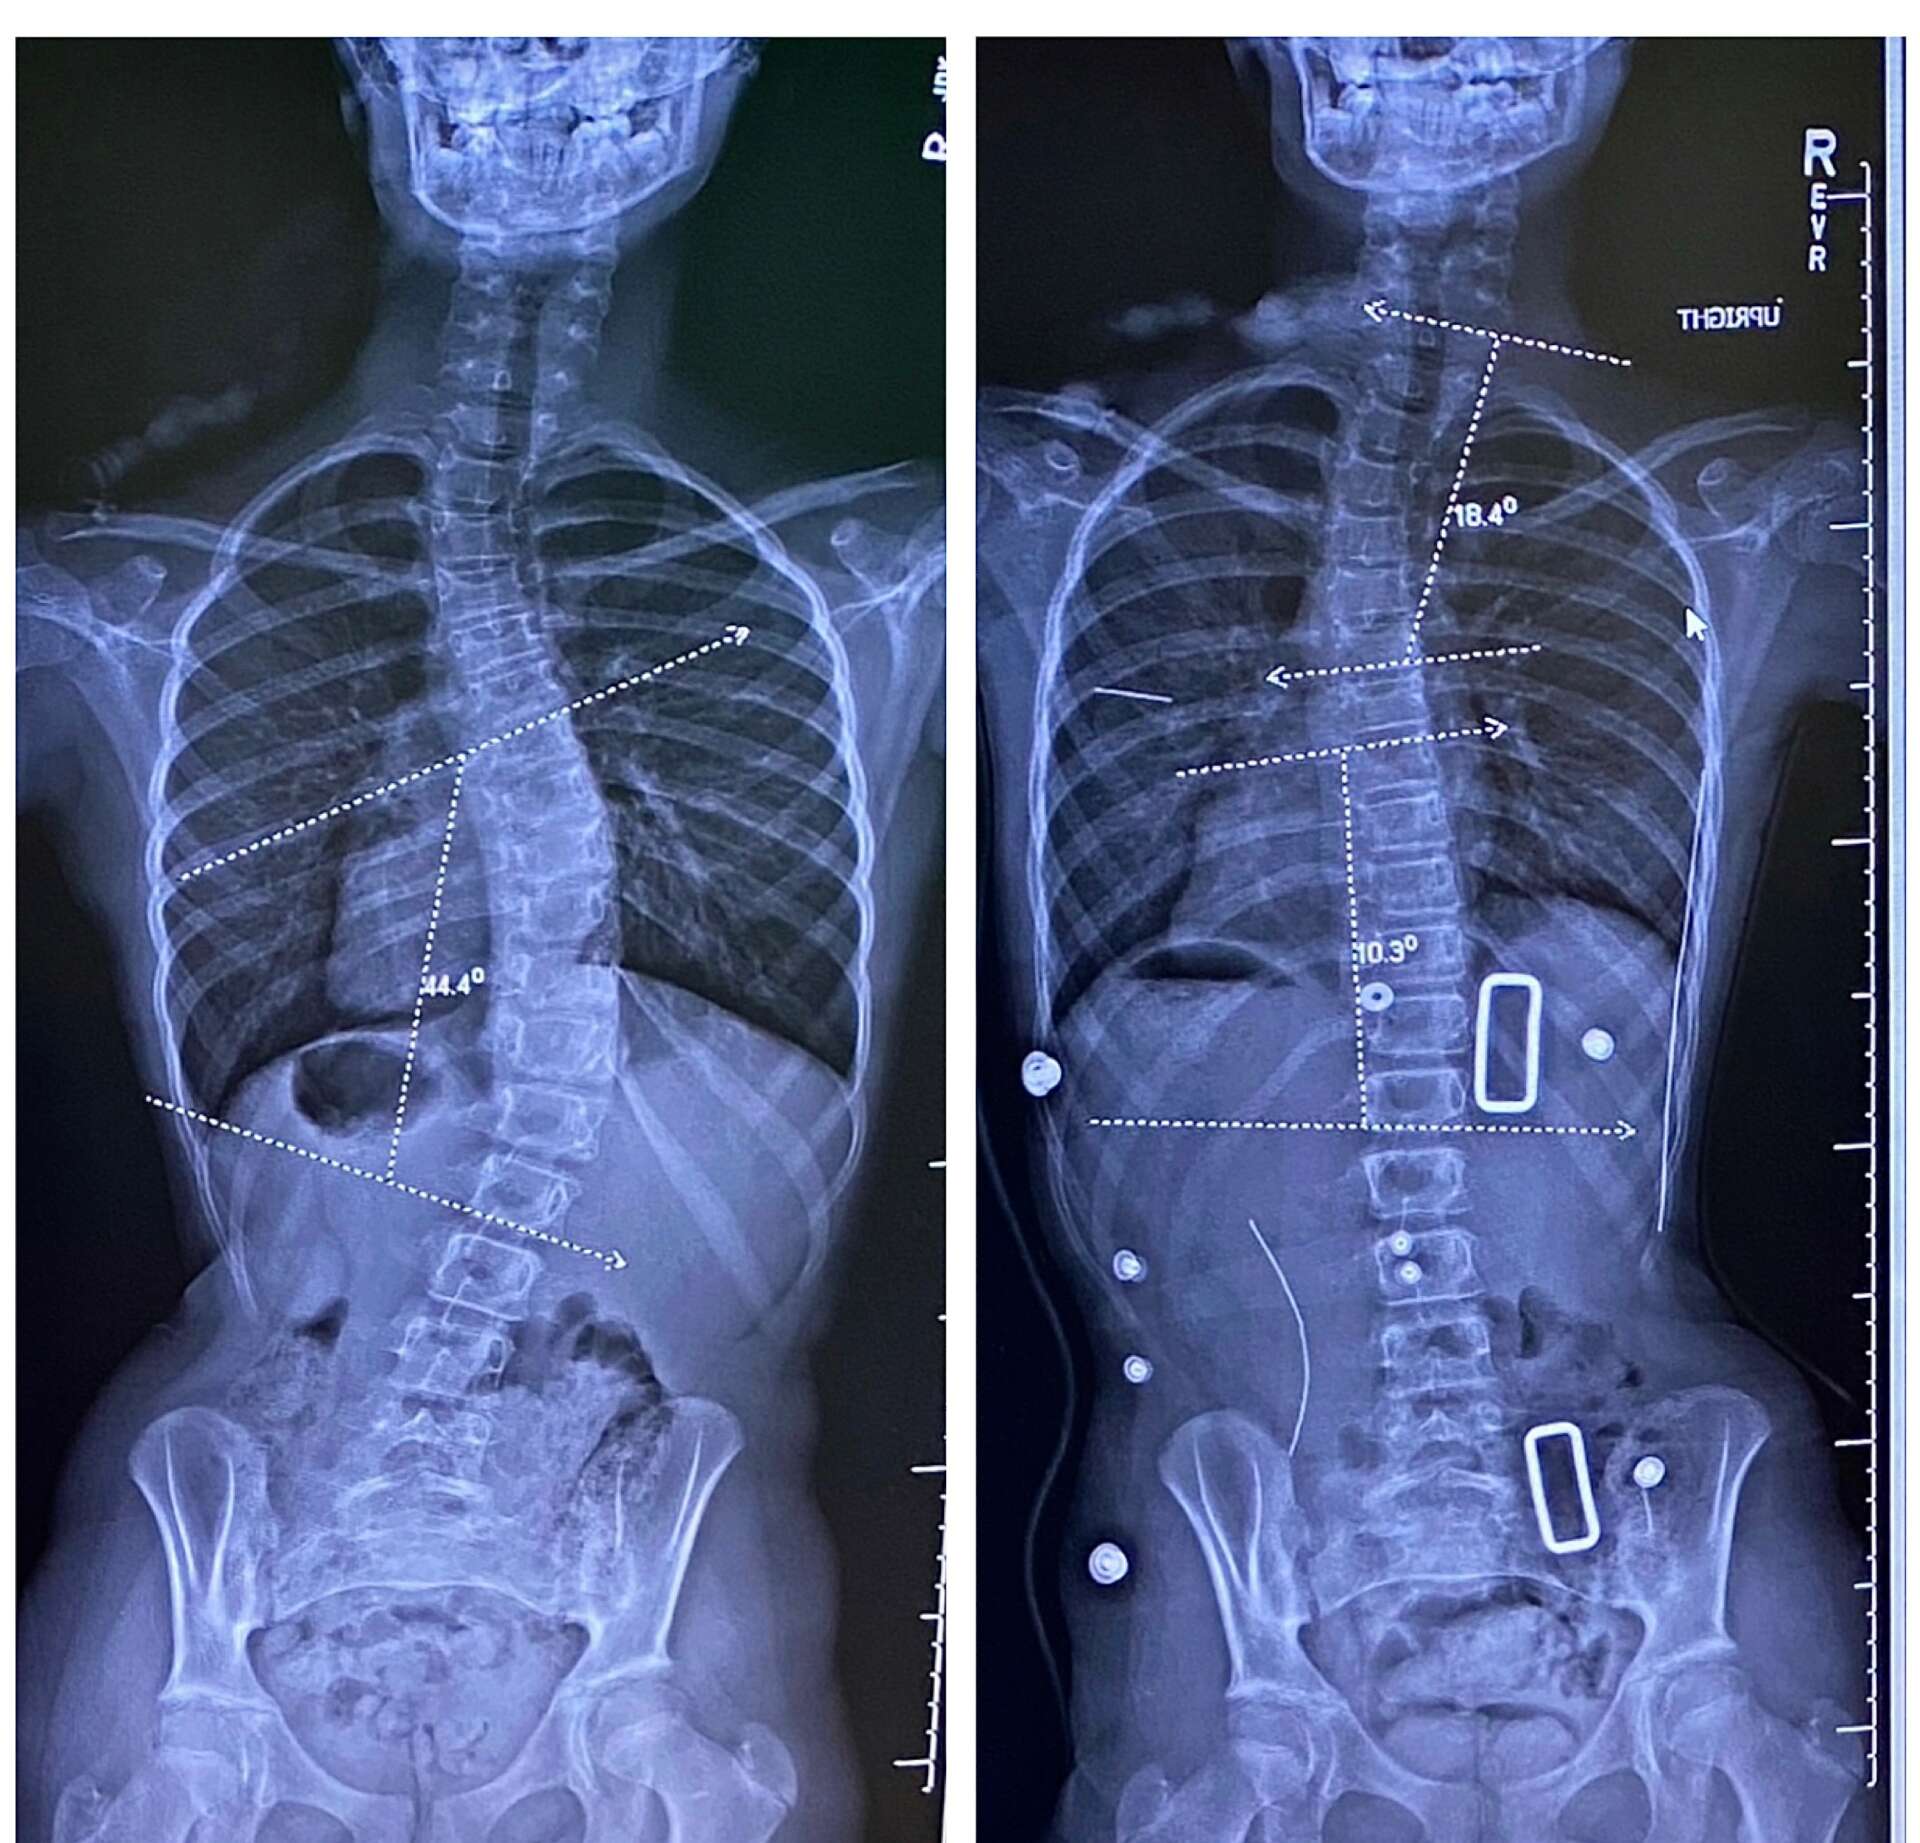

The paradigm for scoliosis treatment in the United States is shifting. 3-dimensional bracing and Schroth Exercise, which have been mainstays of scoliosis treatment in Europe for decades, are finally proliferating in the U.S. Schroth Therapy was only introduced in the U.S. in 2004, Rigo-Cheneau style bracing was introduced shortly afterwards in 2005, but establishing these practices as the standard of care has been a long road. For decades, including the 2000’s, and 2010’s, our treatment options for scoliosis have been “do nothing until the curve is big enough to brace”, “wear a brace”, and “spinal fusion surgery”, with NOTHING in between. Beginning around 2010, studies started popping up in the literature investigating the efficacy Schroth Therapy. Now, it is the most thoroughly studied non-operative scoliosis treatment method available. Many providers still don’t think of recommending physical therapy for scoliosis patients because for so long, it wasn’t even an option. Larger metro areas like New York, LA, and Seattle all have a dozen or so Schroth trained therapists now, but Phoenix has been behind the curve (as has the Southwest as a whole). Thankfully, more and more therapists are becoming certified in the Phoenix area, and Schroth Therapy is starting to trickle into smaller, previously desolate regions for scoliosis treatment. Providers of all types who want to stay up-to-date with best practices for scoliosis should familiarize themselves with the robust body of research, find Schroth trained therapists in their area, and offer physical therapy as an option to their patients.

Scottsdale Scoliosis & Spine Therapy is the largest provider of Schroth Therapy in Arizona. The Schroth Method is the gold standard globally for non-surgical intervention. It differs from traditional physical therapy in that each exercise is designed specifically to address a person’s individual curve. Stock photos cannot represent the detail, the intricacies, and the customization involved in a Schroth Exercise. I spend a lot of time doing education with patients so they understand WHY they are doing their exercises, not just aimlessly reading from a list. This ensures a more comprehensive understanding of your curve pattern, which is essential for autonomy with your scoliosis care. My goal for patients is for me to be the last provider they ever have to see about their scoliosis. I want my patient’s to have an understanding so thorough, so detailed, and so advanced, that they can avoid complications of their scoliosis in the future, and if complications are unavailable, they will understand how to address the problems by themselves.